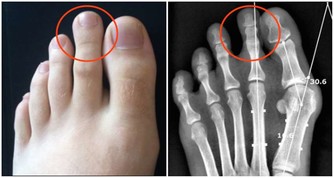

原因三,腸易激綜合徵

為什麼一喝冷水一吃辣就拉肚子

這是一種胃腸道疾病,腸道很容易因為刺激而發生多種不適,一般表現腸道激動→腹痛、腹部不適→排便。另外,還可能伴有腸鳴、腹瀉、放屁、腸道痙攣等多種問題。

飲食上如果吃了冷的、辣的便會發生,一般腹瀉1-2次,便會好轉。除了飲食因素,精神因素,如焦慮、抑鬱都可能導致。這些甚至在喝酒、吃太燙食物之後,也可能發生腹瀉。